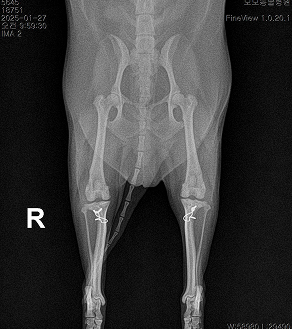

AFTER

수술은 마지막 선택지가 아니라, 아이의 일상과 삶의 질을 지켜주는 기회일 수 있습니다.